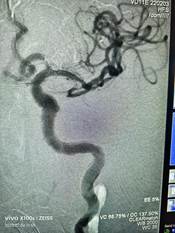

神经介入团队迅速到位。手术选择全麻,穿刺置鞘顺利,但病人高龄、血管迂曲,导引导管到位不理想,Sofia抽吸导管在微导丝、微导管辅助下到达闭塞段,少量造影剂确认导管位置、血栓长度无误后,50ml注射器持续负压抽吸约2分钟后撤出治疗系统,即刻造影证实血管良好复通,前向血流3级。检查抽出血栓量大、泥沙样,Dyct证实未见出血,手术目的达到,病人返ICU监护。

术中